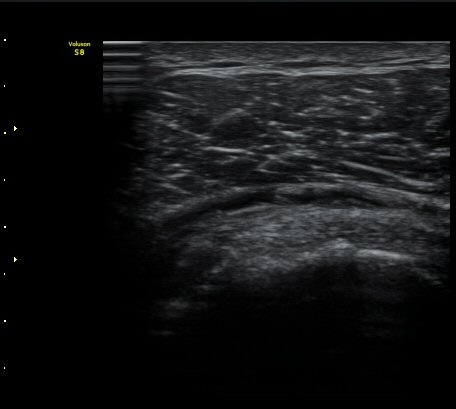

±Ø»ó°Ç Ⱦ´Ü¸é°Ë»ç½Ã ±Ø»ó°Ç ÀϺΠÀú¿¡ÄÚ ºÎÁ¾°ú ¹Ì¼¼ÇÑ °Ç ¿¬°á¼º ¼Ò½ÇÀÌ °üÂûµÊ(±×¸² 4, 5).

±×¸² 4)¿¡¼­ °üÀý¿¬°ñ°æ°è¸é ¡ÈÄ(articular interface sign)°¡ °üÂûµÊ.